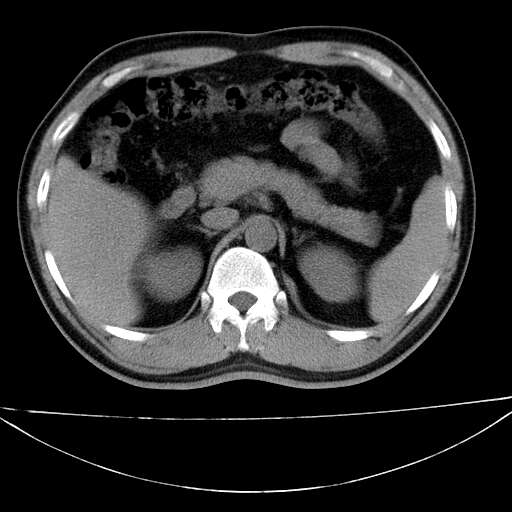

标题: CT21921:腹膜后腔肿物。患者男39Y。体检。增强扫描时间欠准

左侧膈肌脚外缘见一结节样软组织影,密度较均匀,与胸膜关系稍密切,增强轻度强化;考虑来自胸膜良性病变(胸膜纤维瘤可能)。建议加扫胸部ct检查。

1、腹膜后肿物?未见到。

2、左下膈肌脚外缘结节状病变,与胸膜交界面呈锐角,胸膜下脂肪线可见,定位于肺内,考虑支气管囊肿或肺隔离征可能性大。

1)考虑左肺下叶后基底段(或左下胸后壁胸膜)软组织团块,性质待定;建议行进一步检查。2)左肾结石。

左膈肌角后腹膜腔见肿物影,其内见脂肪密度灶及软组织密度灶,强化不明显。病灶大部在后腹膜内。考虑异位嗜铬细胞瘤或脂肪肉瘤、畸胎瘤